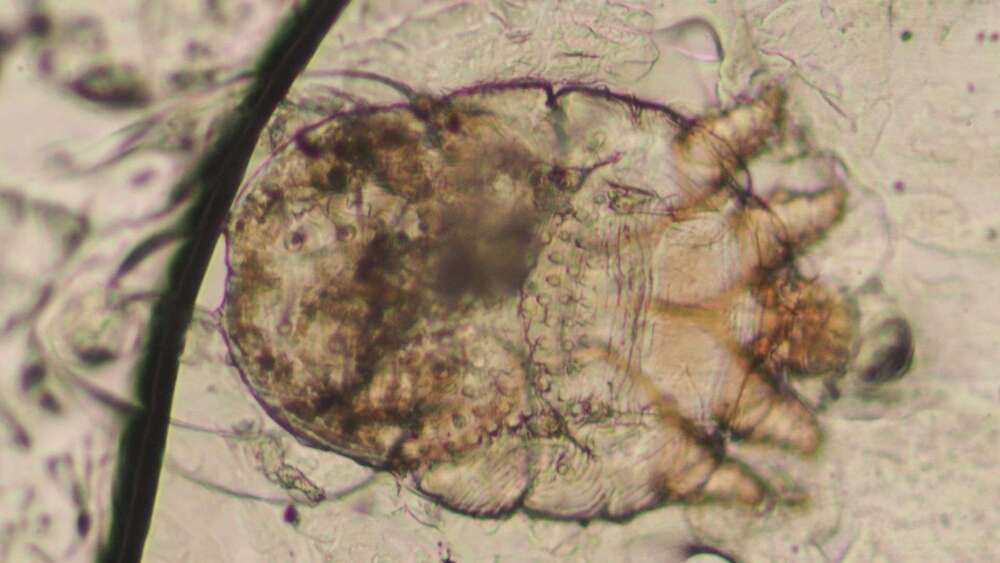

史守正指出,人類疥瘡是一種由人類疥蟲引起的皮膚傳染病,可以在人與人之間持續傳染,常見於人與人近距離密切接觸的場所如醫院、長照機構、軍隊、監獄、庇護所等。疥蟲是一種像蜘蛛有四對腳的螨蟲,沒有翅膀不會飛,不吸人血,只靠皮膚表面的角質與滲出的組織液存活,只是過程中產生的唾液與排泄物及在表皮挖洞時的刺激會引起皮膚過敏反應與癢感。